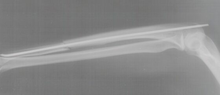

Linker gebrochener Oberarm